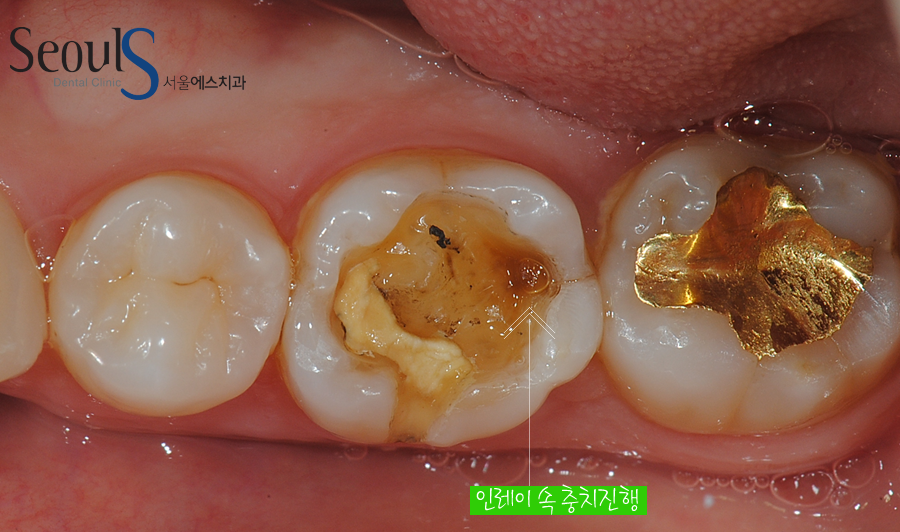

인레이 치료받았던 어금니 속으로 충치가 진행되고 있습니다

치아 속으로 진행되고 있는 충치는 대부분

인레이에 틈이 생겨 그 틈으로 음식물이 들어가 사진과 같이 충치가 진행되게 됩니다

치료받았던 인레이에 틈이 생겼거나 깨져서 음식물이 낄 수 있는 상태가 되면 인레이를 교체해야 합니다

교체하지 않고 계속 사용하면 치아 속으로 음식물이 들어가 충치가 진행되기 때문입니다